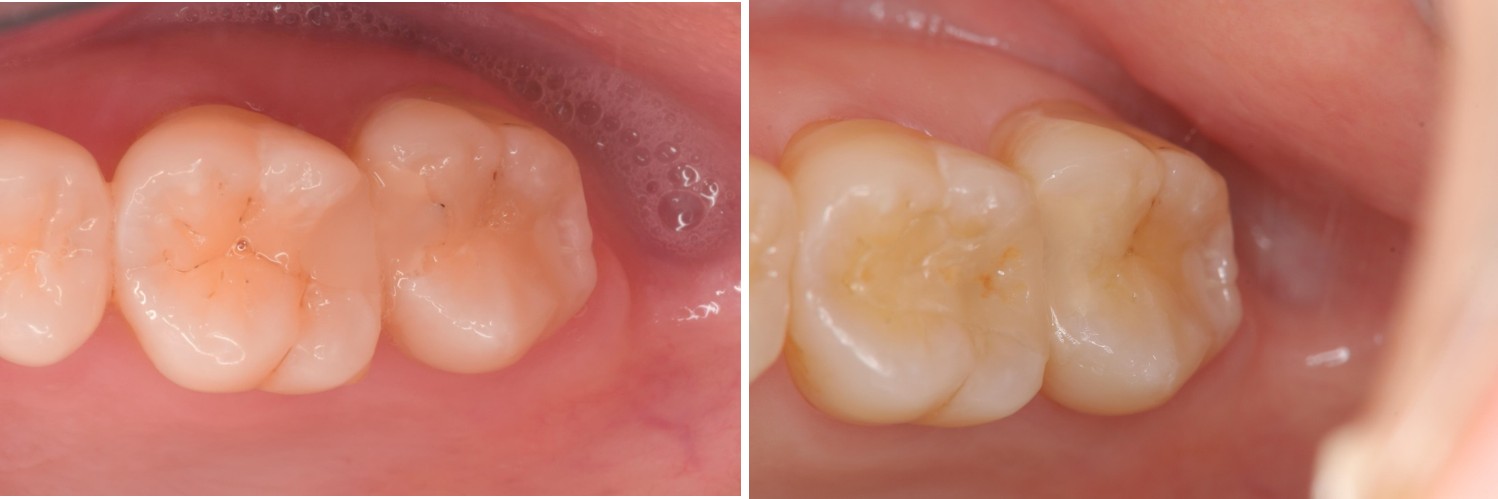

治療前,大臼齒冷熱敏感

治療後,患者適應良好

術前、術後比較